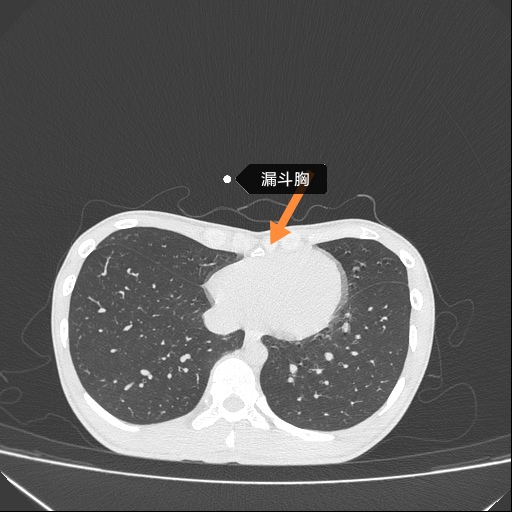

胸外科主任崔健在接诊后,为患者安排查体及影像学检查(图1、图2)。通过检查,发现患者为漏斗胸,诊断明确。在充分分析患者病情的基础上,崔健认为患者符合Nuss手术适应症,在严格进行术前评估及准备,并征求患者及家属的意见后,崔健和胸外科医疗团队为患者实施了Nuss手术,即微创漏斗胸矫正术。术后胸廓矫正满意(图3),患者于术后1周顺利出院。

图1

临床表现[3]:婴儿期漏斗胸压迫症状较轻者常未被注意。患儿常体形瘦弱,不好动,易患上呼吸道感染,活动能力受限制,活动后出现心慌、气短和呼吸困难。体征除胸廓畸形外,常有轻度驼背、腹部凸出等特殊体型。X线侧位胸片可见下段胸骨向后凹陷,与脊柱间距离缩短,CT图凹陷更为确切清晰。